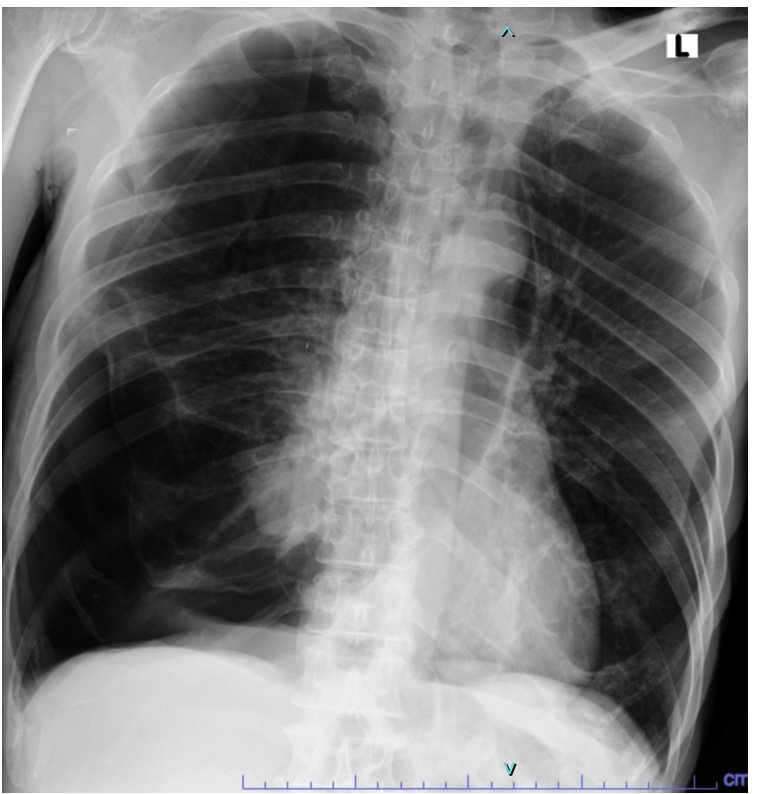

The patient was diagnosed with a second attack of secondary spontaneous pneumothorax and underwent the placement of an indwelling pleural catheter along with oxygen support via a non-rebreathing mask at 14 L/min. Two days later, a bronchoscopy revealed a narrowed lumen in the right middle lobe, likely due to external compression from the air inside the pleural cavity. Bronchoalveolar lavage (BAL) specimens were collected from the right and left sides for microbiological examination. The BAL specimen was then tested using the GeneXpert® MTB/RIF Ultra assay, and the result was negative. Gram staining of the right BAL specimen showed polymorphonuclear cells (3+), indicating an inflammatory process. No bacterial forms were observed in either specimen. The samples were then cultured on blood agar, MacConkey agar, and chocolate agar before incubation. After 24 h of incubation, small, round, convex gram-negative rod-shaped colonies were observed in both the right BAL (Figure 2) and left BAL (Figure 3) specimens. The grown colonies were then identified using the BD Phoenix™ Automated Microbiology System. The identification results confirmed A. baumannii in both right and left BAL specimens. After receiving treatment based on susceptibility testing with trimethoprim-sulfamethoxazole at a dose of 960 mg twice daily for 5 days and undergoing a second wedge resection, the patient’s condition improved.

Figure 2. Acinetobacter baumannii colonies from the right BAL specimen on (a) Blood Agar, (b) Chocolate Agar, and (c) MacConkey Agar